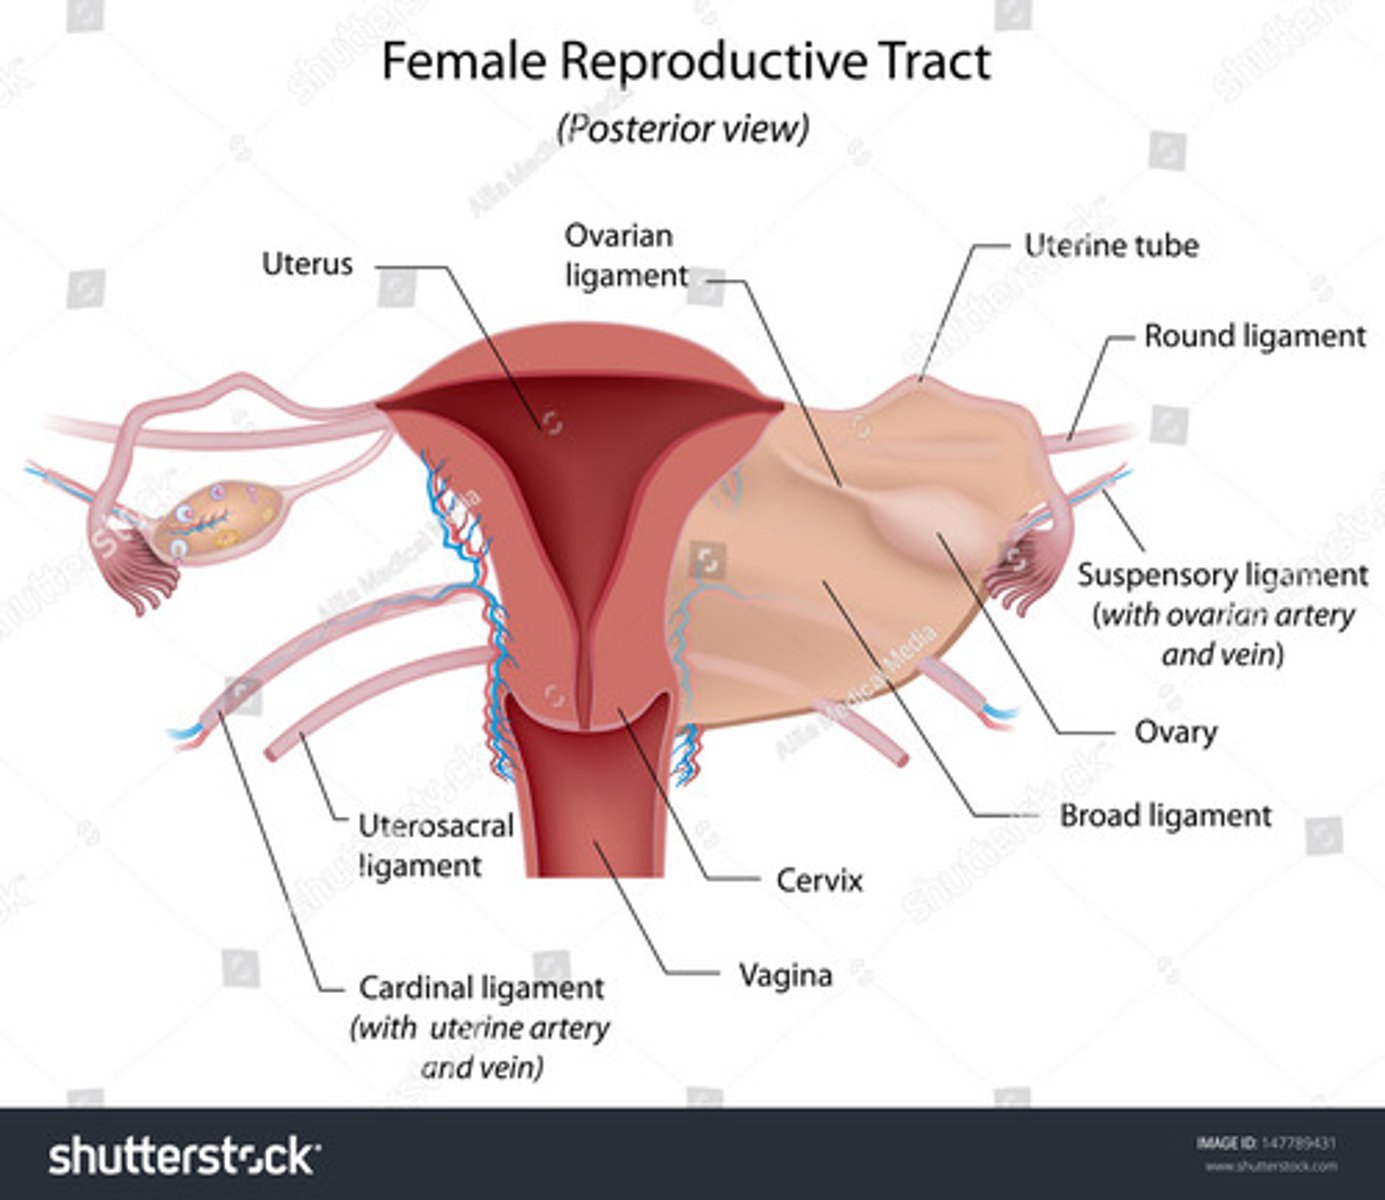

The broad ligaments extend between the ___ and ___

uterine body; ovary

What is positioned between the 2 layers of the broad ligaments?

fallopian tubes

round ligament

ovarian ligament vascular structures

The round ligaments are located ___ to the fallopian tubes and insert into the ___ to help maintain the ___ of the uterus

anteroinferior; labia majora; position

The ovarian ligaments are located ___ at the ___ of the uterus

bilaterally; cornua

The suspensory ligaments extend from the ___ to the ___

infundibulum; pelvic sidewall